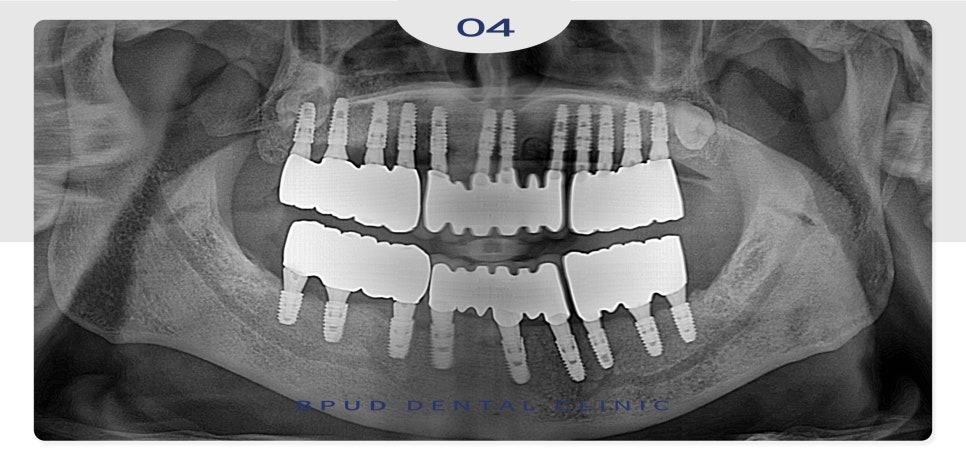

최종 보철물까지 완성하고 난 후에는

틀니보다 훨씬 편하고 심미적이어서

환자분의 만족도는 매우 높으셨습니다.

24.01.23

부평치과 전체임플란트는 식립할 개수가

많으므로 정밀한 식립 위치와 간격, 방향, 깊이를

면밀하게 진단하여야 하며

이를 바탕으로 바르게 식립하여야

보철 진행이 수월하고 관리와 예후가

좋아질 수 있습니다.